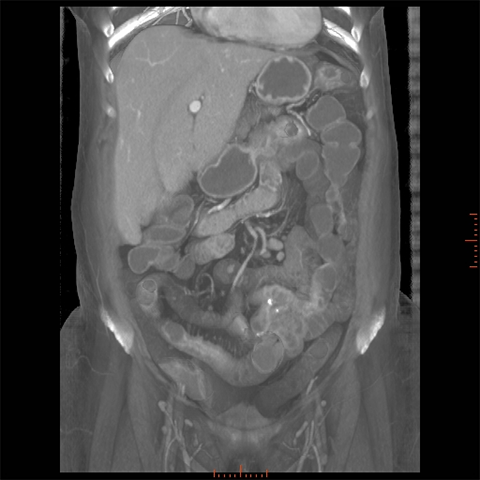

56 year-old male with Crohns Disease presents with persistent abdominal pain and diarrhea. [2 of 4]